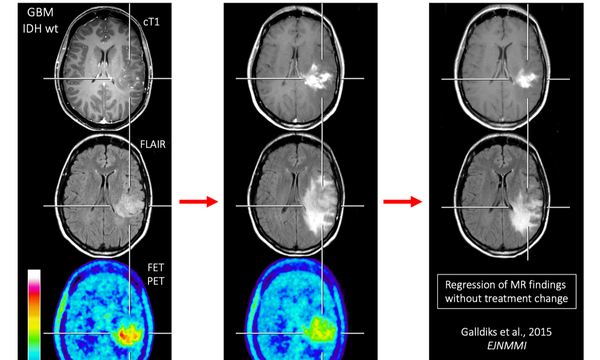

Translationale Bildgebung in der Neuroonkologie

Durch die Arbeitsgruppe werden in der Neuroonkologischen Sprechstunde Patienten mit hirneigenen Tumoren betreut. Mithilfe klinischer und bildgebender Untersuchungen versuchen wir auf die individuellen Bedürfnisse des Patienten ein zugeschnittenes Behandlungskonzept zu erstellen.